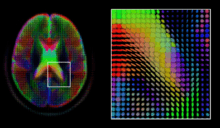

Diffusion MRI

Diffusion MRI is a structural magnetic resonance imaging modality that allows measurement of the diffusion process of molecules. Diffusion is measured by applying a gradient pulse to a magnetic field along a particular direction. In a typical acquisition, a set of uniformly distributed gradient directions is used to create a set of diffusion weighted volumes. In addition, an unweighted volume is acquired under the same magnetic field without application of a gradient pulse. As each acquisition is associated with multiple volumes, diffusion MRI has created a variety of unique challenges in medical image computing.

The diffusion tensor,[43] a 3 × 3 symmetric positive-definite matrix, offers a straightforward solution to both of these goals. It is proportional to the covariance matrix of a Normally distributed local diffusion profile and, thus, the dominant eigenvector of this matrix is the principal direction of local diffusion. Due to the simplicity of this model, a maximum likelihood estimate of the diffusion tensor can be found by simply solving a system of linear equations at each location independently. However, as the volume is assumed to contain contiguous tissue fibers, it may be preferable to estimate the volume of diffusion tensors in its entirety by imposing regularity conditions on the underlying field of tensors.[44] Scalar values can be extracted from the diffusion tensor, such as the fractional anisotropy, mean, axial and radial diffusivities, which indirectly measure tissue properties such as the dysmyelination of axonal fibers [45] or the presence of edema.[46] Standard scalar image computing methods, such as registration and segmentation, can be applied directly to volumes of such scalar values. However, to fully exploit the information in the diffusion tensor, these methods have been adapted to account for tensor valued volumes when performing registration [47][48] and segmentation.[49][50]

Given the principal direction of diffusion at each location in the volume, it is possible to estimate the global pathways of diffusion through a process known as tractography.[51] However, due to the relatively low resolution of diffusion MRI, many of these pathways may cross, kiss or fan at a single location. In this situation, the single principal direction of the diffusion tensor is not an appropriate model for the local diffusion distribution. The most common solution to this problem is to estimate multiple directions of local diffusion using more complex models. These include mixtures of diffusion tensors,[52] Q-ball imaging,[53] diffusion spectrum imaging [54] and fiber orientation distribution functions,[55][56] which typically require HARDI acquisition with a large number of gradient directions. As with the diffusion tensor, volumes valued with these complex models require special treatment when applying image computing methods, such as registration [57][58][59] and segmentation.[60]